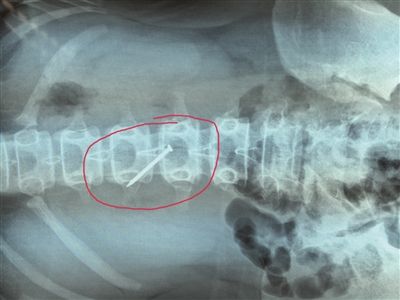

長約4厘米的鐵釘被取出時(shí),已刺穿13歲女生的胃壁。 朱鼎兆 攝

一根長近4厘米的鐵釘在胃里會(huì)怎么樣?29日下午4時(shí)許,在淮安市婦幼保健院,該院小兒科醫(yī)生就從宿遷泗陽一名13歲女生小軒(化名)的胃里成功取出一根長約4厘米的鐵釘,而此時(shí),這根鐵釘已經(jīng)刺破了小軒的胃壁。